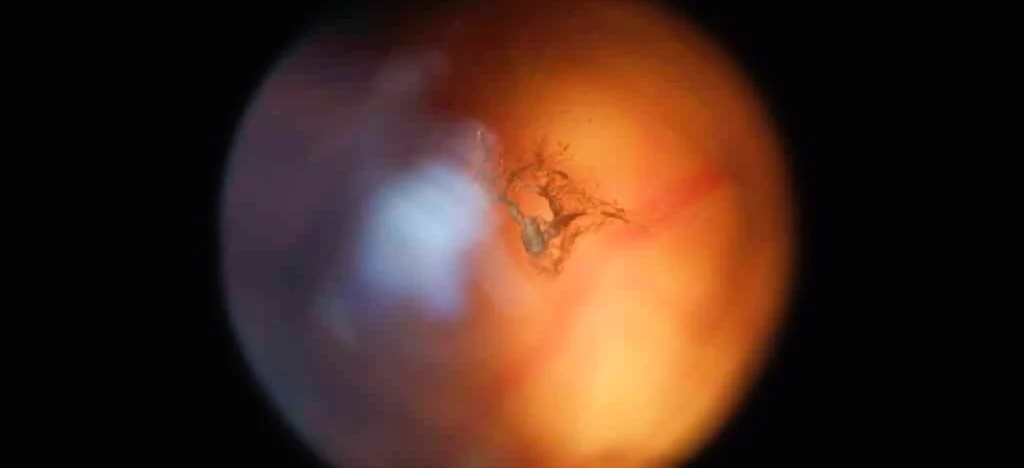

Retina Yırtılması Nedir? En Çok Merak Edilen 5 Soru